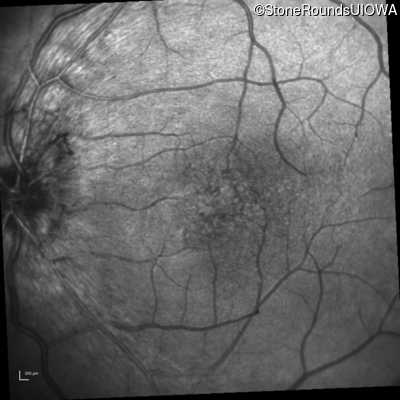

Infrared Fundus Photograph - Right - 20/30 -2

Exemplar